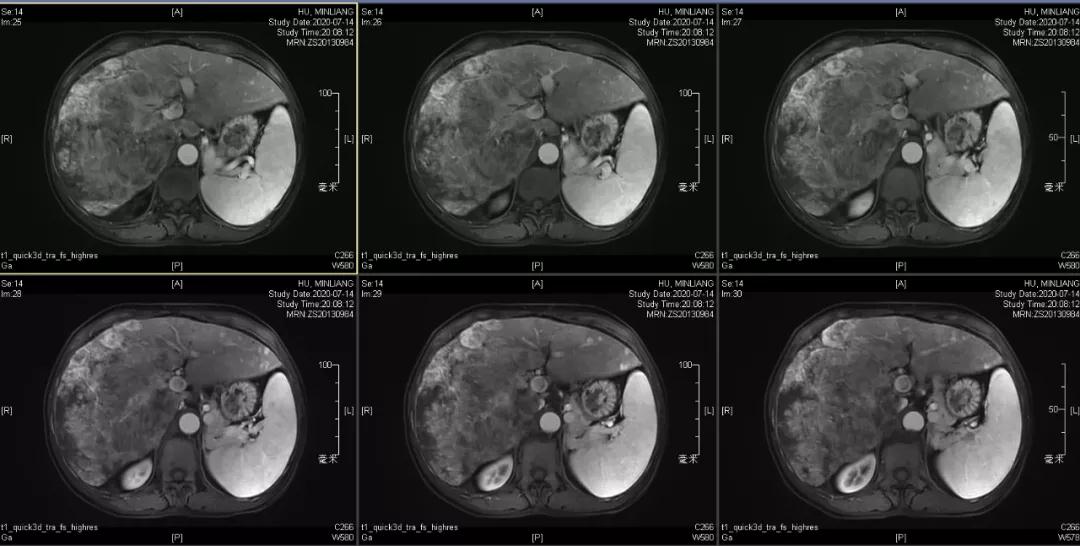

肝脏弹性超声:12kPa。腹部MRI平扫+增强:肝巨块结节性HCC(最大径18.4cm)伴肝内多发转移(最大径3.5cm),肝右静脉广泛癌栓形成;肝硬化伴门脉高压、脾大、少量腹水;肝囊肿;双肺多发转移。胸部CT平扫:两肺多发转移,两肺气肿伴肺大泡,两肺散在慢性炎症,右侧少量胸水。

Δ肝脏MRI,最大肿瘤18.4cm

肿瘤学评估(用药后2个月对比6个月):肝内主瘤明显缩小,动脉期强化降低;子灶消失;门脉右支癌栓明显缩小坏死;肺转移灶缩小,大部分消失。

Δ治疗过程中病灶影像学变化